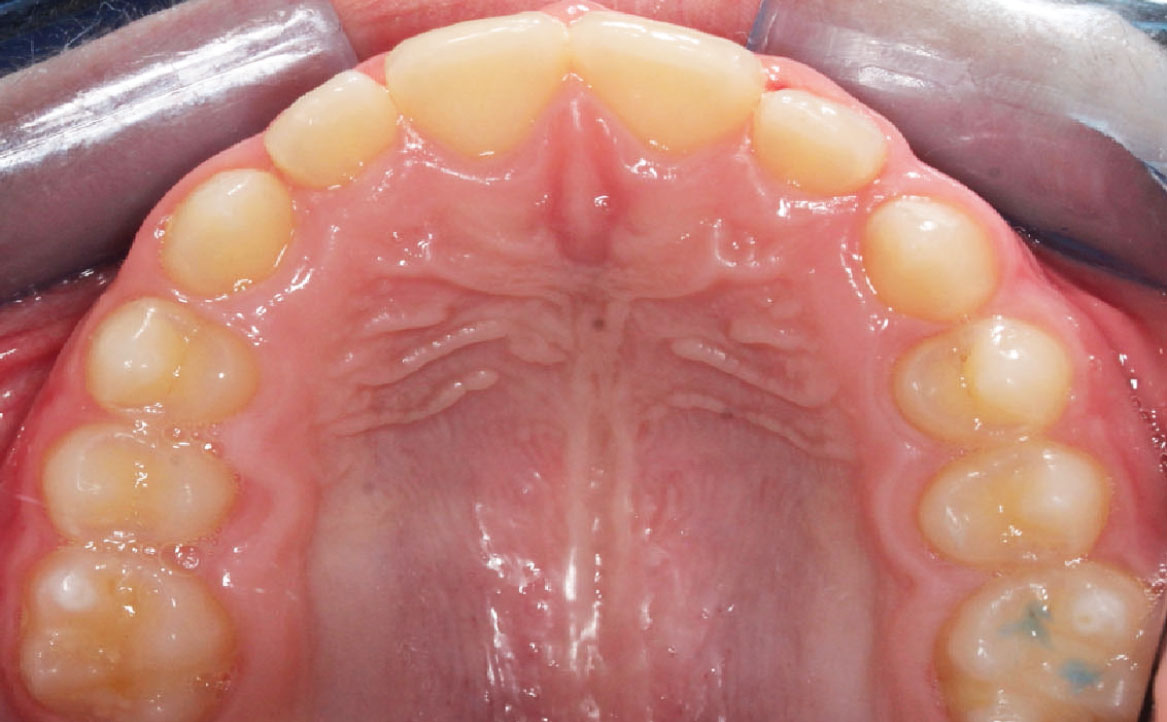

L’overjet e l’overbite sono entrambi ridotti in massima intercuspidazione. Trasversalmente il mascellare superiore è contratto (fig. 4-7).

Fig. 6A Foto dell'arcata superiore.